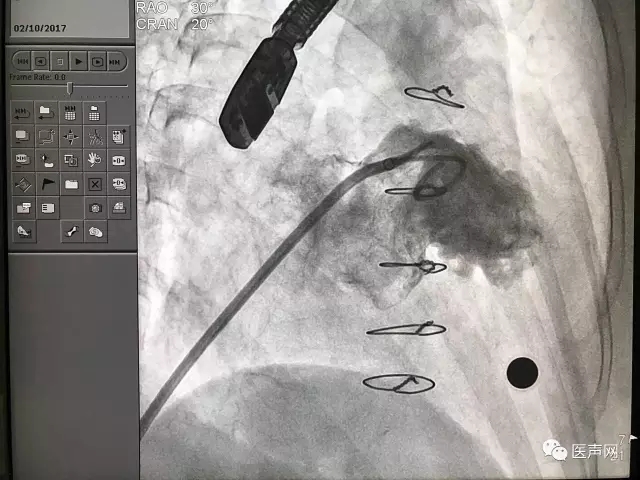

ACP成功释放